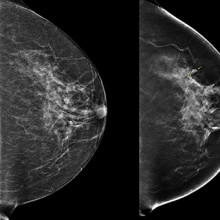

(Left) 2D mammogram image of left breast, where no lesion was visible. (Right) 3D tomographic image of the same breast showing a lesion, indicated by arrows.

During a conventional digital 2D mammogram, two x-ray images are taken of the breast, one from top-to-bottom and another from side-to-side at an angle. This technology is limited by the overlapping breast tissue that occurs from the required compression of the breast, and breast abnormalities may be hidden.

A tomosynthesis exam is relatively new technology in which the x-ray tube moves in an arc over the compressed breast and captures multiple images from different angles. The images are then reconstructed into a set of 3D images by a computer. By being able to examine the breast at multiple layers of depth, the radiologist is better able to distinguish normal breast tissue from potential abnormalities. It is therefore assumed that tomosynthesis may solve some challenges associated with standard mammography, and could be especially useful for women with dense breast tissue.